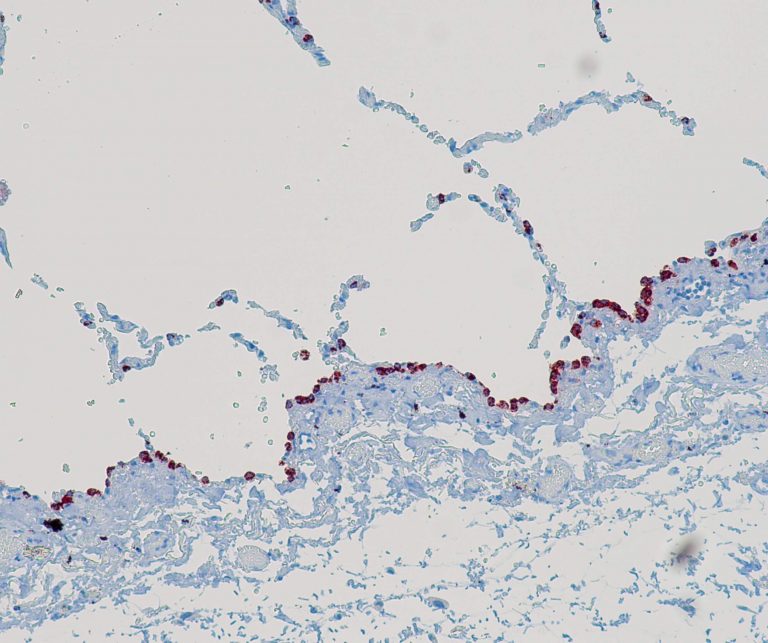

Vascular Pathology

Gastrointestinal (GI) Pathology

General Marker

Breast Pathology

Endocrine Pathology

Gynecological Pathology

Neuropathology

Infection Markers

Lung Pathology

Urinary Tract Pathology

Transplantation Pathology

Soft Tissue Pathology

Hematopathology